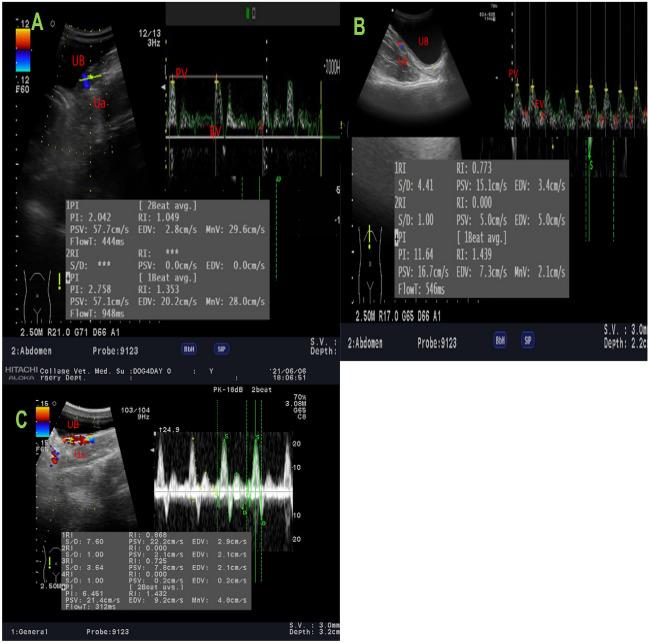

One of the most prevalent disorders of the urinary system is urinary tract infection, which is mostly brought on by uropathogenic Escherichia coli (UPEC). The objective of this study was to evaluate the regenerative therapeutic and antibacterial efficacy of PRP for induced bacterial cystitis in dogs in comparison to conventional antibiotics. 25 healthy male mongrel dogs were divided into 5 groups (n = 5). Control negative group that received neither induced infection nor treatments. 20 dogs were randomized into 4 groups after two weeks of induction of UPEC cystitis into; Group 1 (control positive; G1) received weekly intravesicular instillation of sodium chloride 0.9%. Group 2 (syst/PRP; G2), treated with both systemic intramuscular antibiotic and weekly intravesicular instillation of PRP; Group 3 (PRP; G3), treated with weekly intravesicular instillation of PRP, and Group 4 (syst; G4) treated with an intramuscular systemic antibiotic. Animals were subjected to weekly clinical, ultrasonographic evaluation, urinary microbiological analysis, and redox status biomarkers estimation. Urinary matrix metalloproteinases (MMP-2, MMP-9) and urinary gene expression for platelet-derived growth factor -B (PDGF-B), nerve growth factor (NGF), and vascular endothelial growth factor (VEGF) were measured. At the end of the study, dogs were euthanized, and the bladder tissues were examined macroscopically, histologically, and immunohistochemically for NF-κB P65 and Cox-2. The PRP-treated group showed significant improvement for all the clinical, Doppler parameters, and the urinary redox status (p < 0.05). The urinary MMPs activity was significantly decreased in the PRP-treated group and the expression level of urinary NGF and VEGF were downregulated while PDGFB was significantly upregulated (p < 0.05). Meanwhile, the urinary viable cell count was significantly reduced in all treatments (P < 0.05). Gross examination of bladder tissue showed marked improvement for the PRP-treated group, expressed in the histopathological findings. Immunohistochemical analysis revealed a marked increase in Cox-2 and NF-κB P65 in the PRP-treated group (P < 0.05). autologous CaCl2-activated PRP was able to overcome the bacterial infection, generating an inflammatory environment to overcome the old one and initiate tissue healing. Hence, PRP is a promising alternative therapeutic for UPEC cystitis instead of conventional antibiotics.